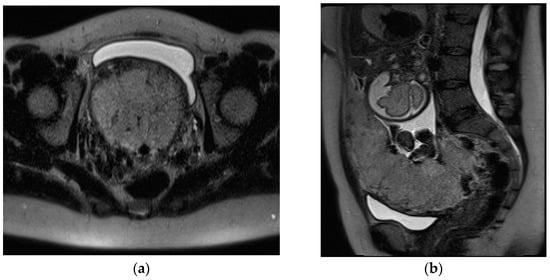

RPOC is defined by intrauterine retention of residual placental or trophoblastic tissue, representing one of the most common causes of post-abortion or postpartum hemorrhage [99]. RPOC complicates 1% of all full-term pregnancies, occurring more frequently after second-trimester miscarriage or surgical pregnancy termination with a reported rate of 6%. In women who underwent medical abortions, a prevalence up to 15% is reported [100]. RPOC associated with PAS has increased, especially in patients who have achieved pregnancy through assistive reproductive technology [101]. The clinical symptoms of RPOC include vaginal bleeding, pelvic pain, and fever. Although an accurate and timely diagnosis of RPOC represents a challenge, it is crucial for guiding proper management. Transvaginal US is the first-line imaging modality and a useful diagnostic tool in differentiating RPOC from normal intrauterine lochia and clots [99]. The main US features of RPOC include a thickened endometrium (ranging from 8 to 13 mm) and a variable amount of heterogeneous and echogenic material within the endometrial cavity, sometimes presenting as a mass, with vascular flow at Color Doppler US [8]. Sellmeyer et al. observed that the detection of any vascularity in a thickened endometrial echo complex (EEC) or mass is likely to represent RPOC with a predictive positive value of 96%; however, the lack of vascularity at Color Doppler US does not exclude the diagnosis of RPOC [99]. Four vascularity patterns have been established, in which the degree of vascularity of the endometrial versus the myometrial component is compared in the same image section and classified as type 0, 1, 2, or 3. Type 0 vascularity, defined as no detectable vascularity in a thickened EEC or mass, may correspond to a blood clot or avascular RPOC. The vascular patterns 1–3 show an increasing flow of endometrium compared to myometrium, helping the clinical management of RPOC [8,99]. Type 3, defined as marked endometrial vascularity (higher than that of normal myometrium in the same US section), has a PPV of 100%; in these patients, flow can be so robust as to mimic a uterine arteriovenous malformation (AVM). However a mass in the puerperal uterus with vascularity on US is much more likely to represent RPOC than uterine AVM. AVMs can be considered when RPOC have been ruled out and Color Doppler US demonstrates serpiginous tubular vascular structures centered in the myometrium [102]. When US is inconclusive, CT or MRI should be performed. On MRI, RPOC appear as intracavitary uterine soft-tissue mass with variable T1 and T2 signal intensities, depending on the degree of bleeding and necrosis (Figure 9).

Post-contrast MRI is useful to assess the enhancement, which is also heterogeneous (and can be partial, complete, or delayed). Other features to take into account are a variable degree of associated myometrial thinning and obliteration of the junctional zone [8,103]. The aforementioned US and MRI findings can overlap with those of gestational trophoblastic disease (GTD), a broad spectrum of clinical and histopathological entities arising from uncontrolled growth of trophoblastic tissue and including hydatiform moles (complete and partial), invasive moles, choriocarcinoma, and placental site trophoblastic tumor [104]; therefore, clinical and lab context are crucial. Specifically; the serum β human chorionic gonadotropin (beta hCG) value is typically normal or low in women with RPOC and significantly increased in those with GTD [103]. GTD should be considered in the differential diagnosis of hemorrhagic conditions with a positive pregnancy test after a delivery, a miscarriage, or a query ectopic.